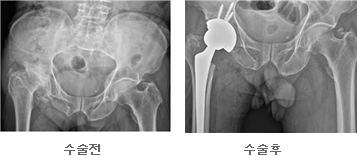

엉덩이 관절을 이루는 골반의 비구나 대퇴골의 머리부분이 닳거나(퇴행성 질환) 특정질병에 의해 괴사되거나, 충격등에 의해 손상된 관절을 모두 인공으로 만든 삽입물로 교체하는 시술을 말한다. 인공 엉덩이관절 치환술의 수술 대상으로는 퇴행성 관절염, 류마티스성 관절염, 대퇴골두 무혈성괴사등으로 인한 고관절(비구,대퇴골의 머리부분)의 손상이 심한 경우 일차적인 수술 대상이 되지만 병이 있다고 해서 모두 수술해야하는 것은 아니다. 어느 정도의 관절에 문제가 있더라도 심한 통증이 없는 경우에는 인공 관절 시술을 받을 필요가 없다. 가만히 있을 때도 아프며 통증으로 인하여 생활이 잘 안되고 잠을 못 자는 경우, 통증이나 관절구축으로 인하여 고관절의 움직이는데 제한이 심한 경우가 그 대상이 된다. 또한 최근 인공 관절 재질의 발달로 시술을 받는 나이 제한이 어느 정도는 둔화 되었지만 그래도 가능한 한 젊은 나이는 피하는 게 좋다.